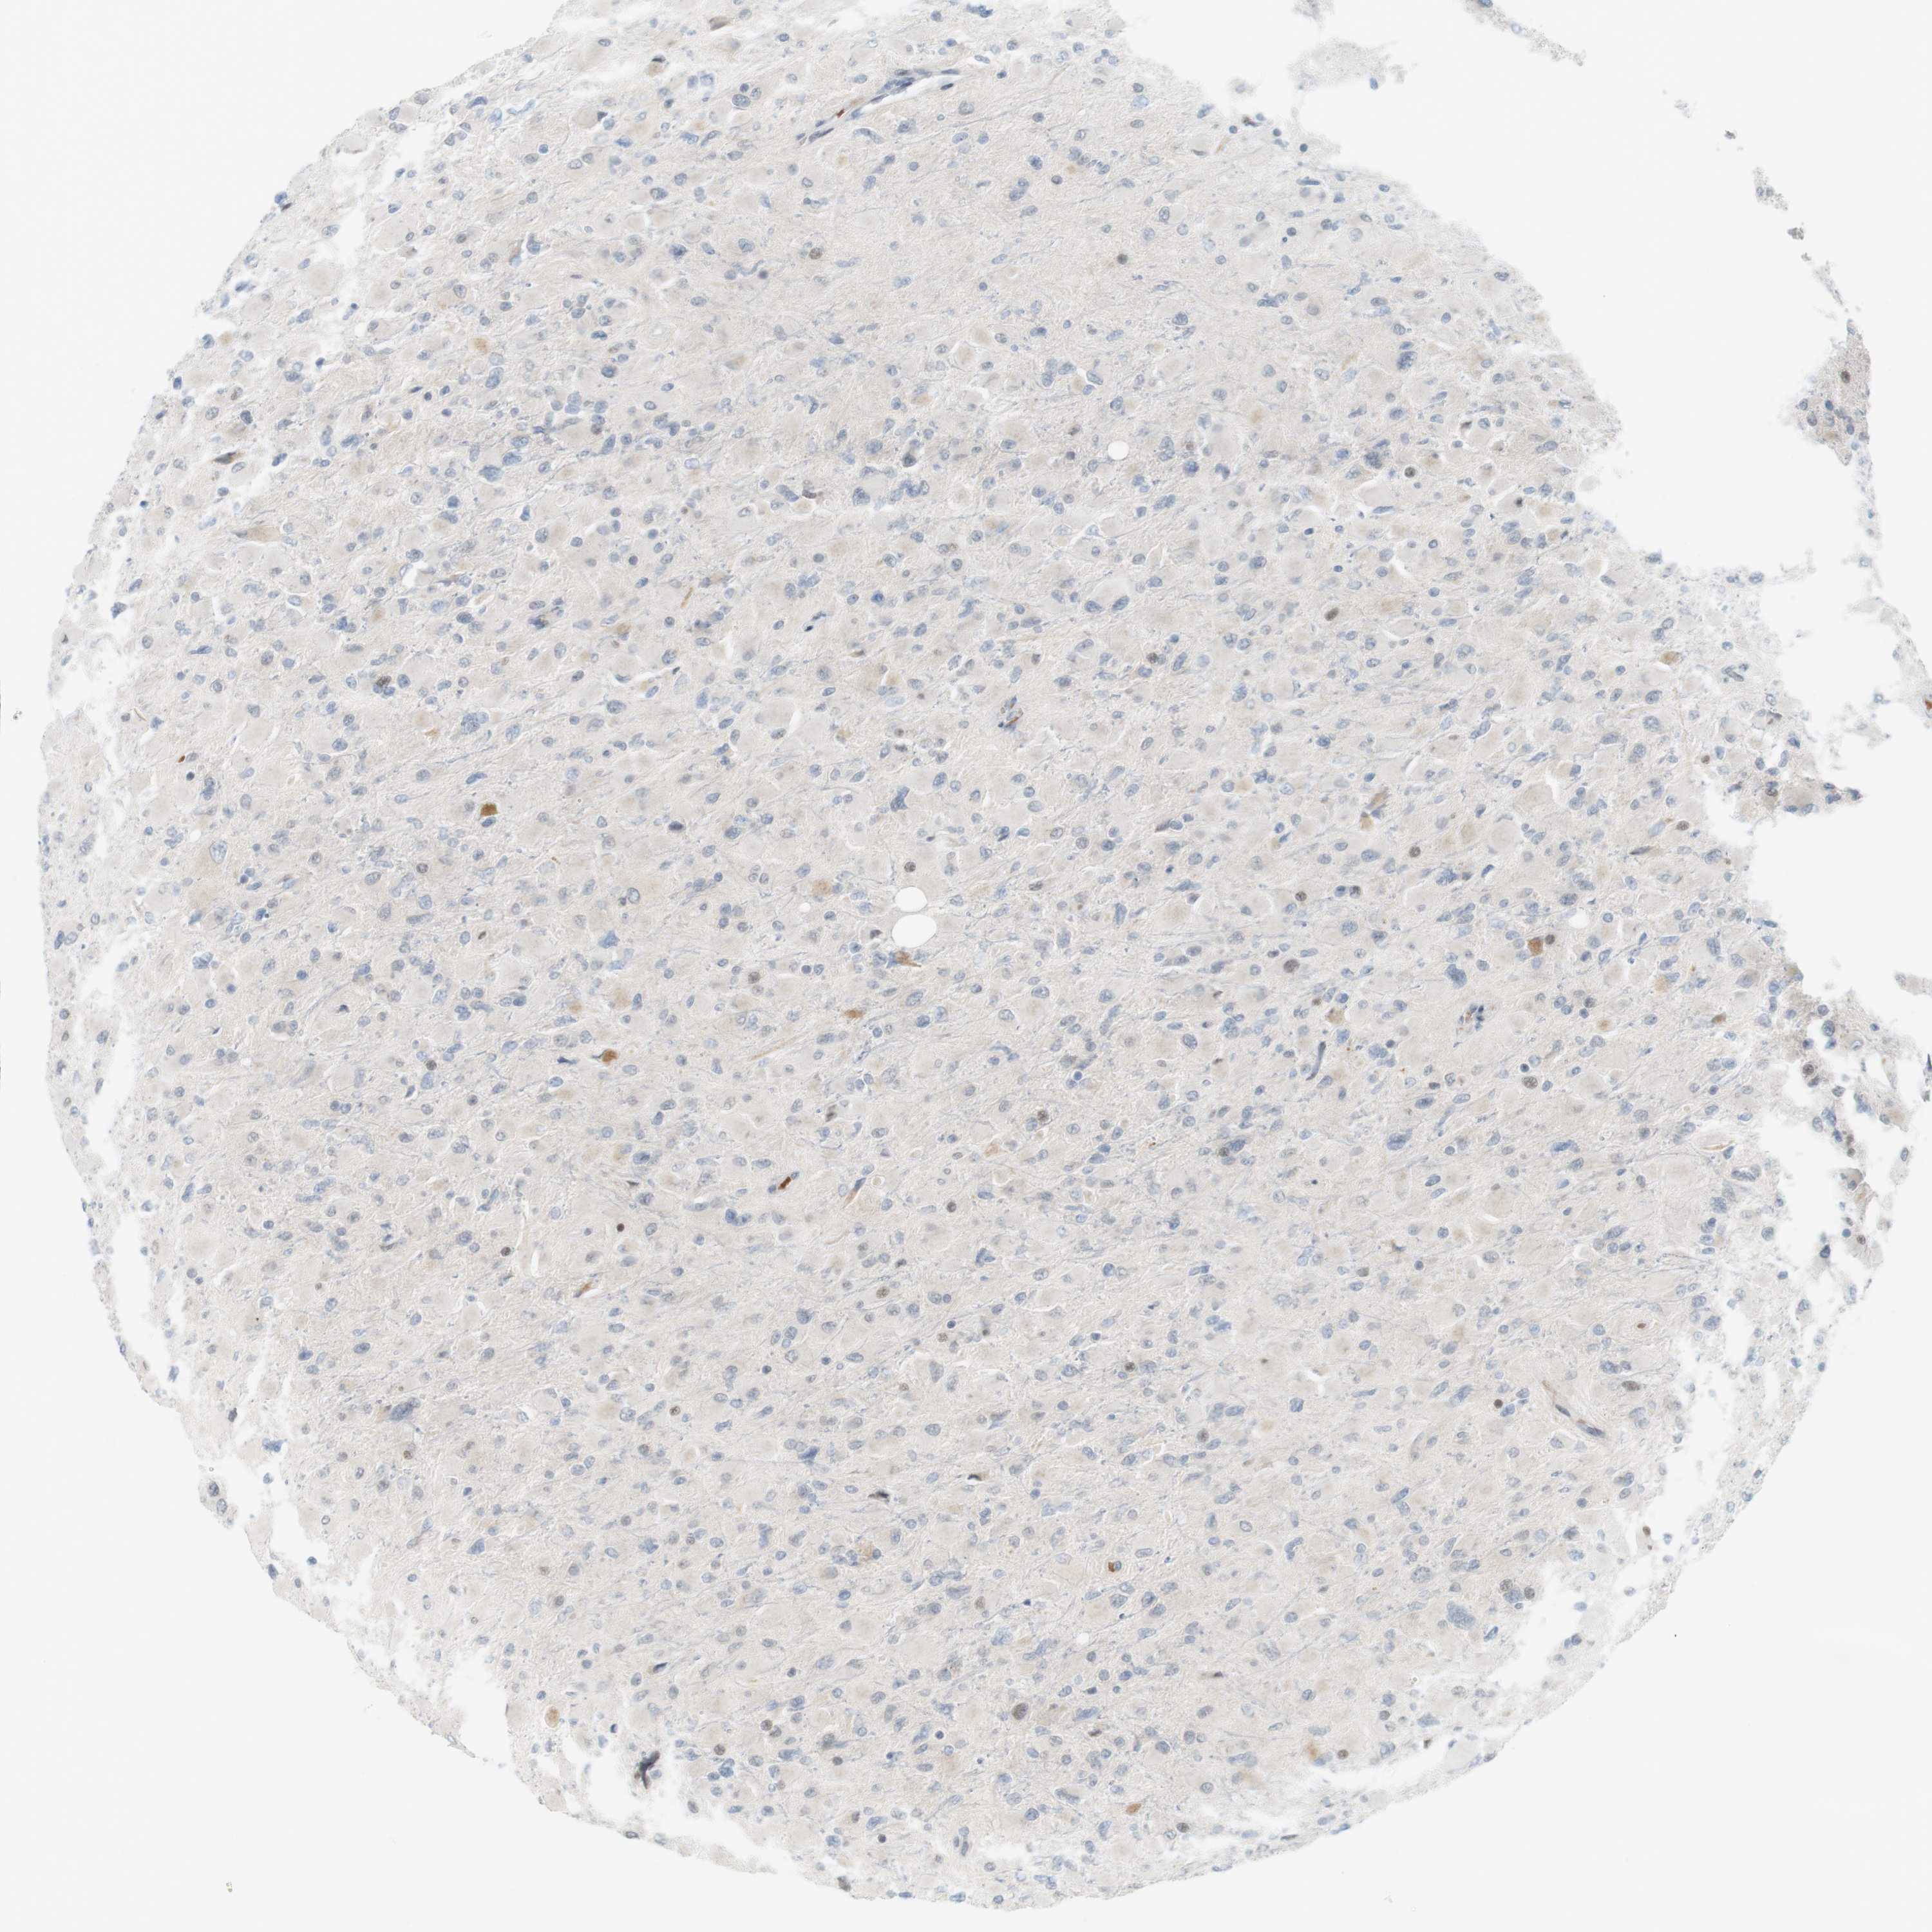

GLIOMA - Protein expressioni

A mouse-over function shows sample information and annotation data. Click on an image to view it in a full screen mode. Samples can be filtered based on level of antibody staining by selecting one or several of the following categories: high, medium, low and not detected. The assay and annotation is described here.

Note that samples used for immunohistochemistry by the Human Protein Atlas do not correspond to samples in the TCGA dataset.

Antibody stainingi

Antibody staining in the annotated cell types in the current human tissue is reported as not detected, low, medium, or high, based on conventional immunohistochemistry profiling in selected tissues. This score is based on the combination of the staining intensity and fraction of stained cells.

Each image is clickable and will lead to virtual microscopy that enables deeper exploration of all samples and also displays staining intensity scores, fraction scores and subcellular localization as well as patient and tissue information for each sample.

Antibody HPA001232

Antibody CAB015397

Staining

High

Medium

Low

Not detected

Intensity

Strong

Moderate

Weak

Negative

Quantity

>75%

75%-25%

<25%

None

Location

Nuclear

Cytoplasmic/membranous

Cytoplasmic/membranous,nuclear

Glioma, malignant, High grade

Glioma, malignant, Low grade